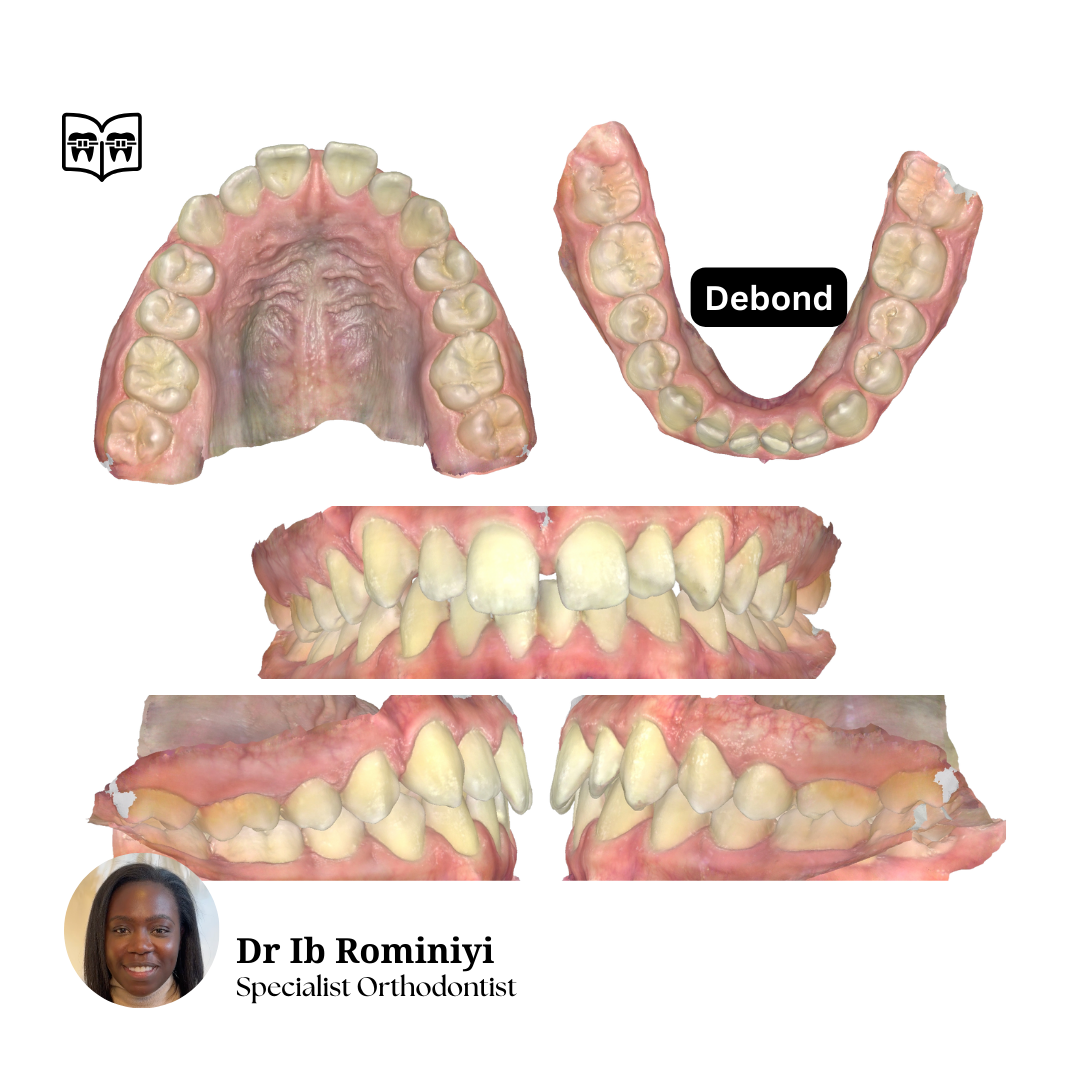

Class 1: Upper spacing, lower mild crowding

Plan: Non-extraction, U+L fixed appliances, retain